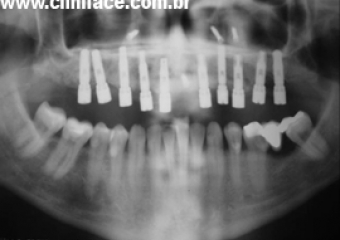

Raio X após instalação dos implantes